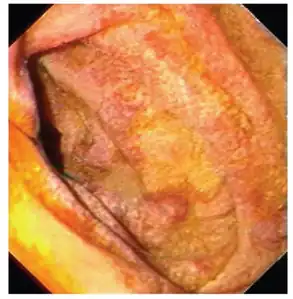

Endoscopy of the duodenum and jejunum can reveal pale yellow shaggy mucosa with erythematous eroded patches in patients with classic intestinal Whipple's disease, and small bowel X-rays may show some thickened folds. Other pathological findings may include enlarged mesenteric lymph nodes, hypercellularity of lamina propria with "foamy macrophages", and a concurrent decreased number of lymphocytes and plasma cells, per high power field view of the biopsy.

Mucosa is swollen and grey-yellowish -

High magnification micrograph showing the characteristic foamy macrophages in the lamina propria, H&E stain